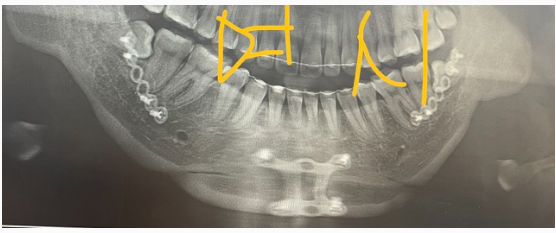

악(顎)교정술(턱의 위치나 모양을 변형시키는 수술)의 일종으로 윗턱인 상악(上顎)과 아랫턱인 하악(下顎)을 함께 수술하는 경우 양악(兩顎)수술이라 칭한다. 쉽게 말해 코 밑부터 아래턱 뼈 부분을 잘라내서 턱을 축소시켜, 얼굴을 바꾸는 치과 영역의 대수술.

양악수술을 하는 방법은 상악과 하악의 뼈를 잘라서 2개로 분리한 다음 정상 교합에 맞게 상악과 하악의 뼈를 이동시키고 이동된 뼈를 고정하는 방법이다. 뼈를 이동하는 대수술인 만큼 수술은 전신마취로 진행되며 보통 3일~7일 정도 입원하게 된다.

양악수술 한 사람의 엑스레이 상태